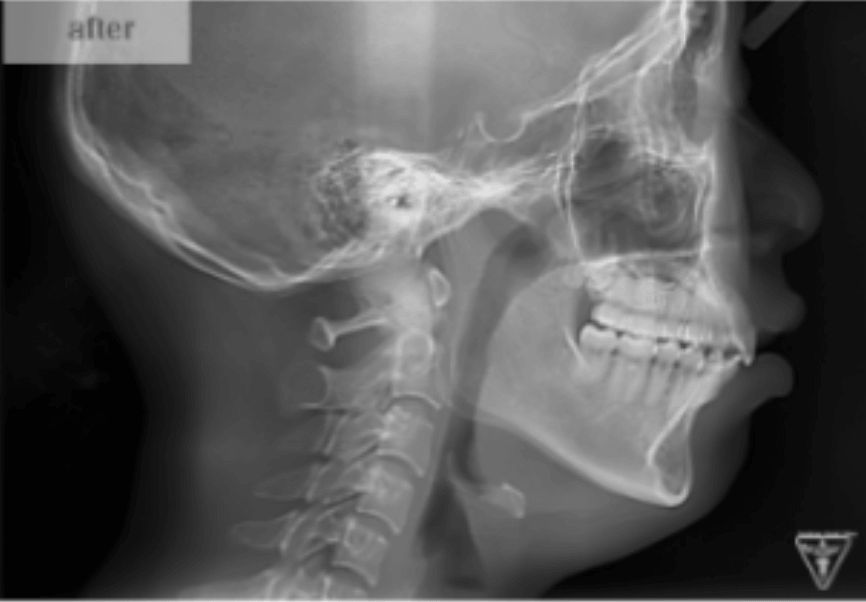

治療後

治療前後の比較